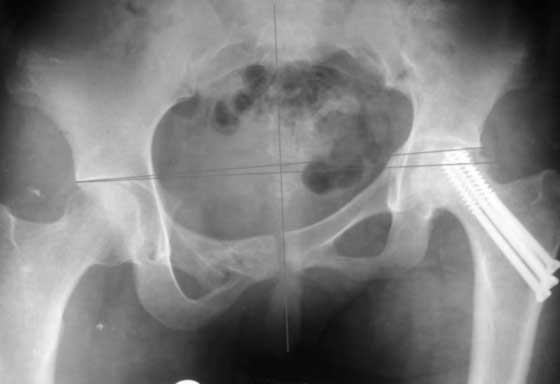

Согласен с Рунковым. Девочка молодая. Имеется ассиметричное расположение вертлужных впадин в прямой проекции. Так как повреждение таза было вертикально-нестабильное, вероятно имеется так же ассиметрия в передне-заднем направлении. Конечно протезом можно компенсировать имеющееся укорочение, но ассиметрично расположенные тазобедренные суставы приведут к нарушению двигательного стереотипа, нарушение походки, остеохондроз и т.д.

Привет, Макс. Не торопись, посмотри внимательно на истинную картину. Толстая стрелка указывает на нижний край смещенного кп сочленения.

разговоров нет, смещение значимое, какое оно было, такое и осталось. Будут проблемы и с сидением и с осанкой и т.д. Идеальным вариантом было бы, конечно, исправить деформацию, а потом запротезировать. Но... цена вопроса. сейчас деформация, судя по костной мозоли, стабильная, и таз несет основную свою функцию - опорную, явно КПС не болит. Превратить стабильную деформацию в нестабильную и потом ее исправить - задача непростая, но выполнимая. Оперативное лечение будет сложное, скорее всего многоэтапное и длительное. С определенными рисками, общехирургическими и специфическими, например несращение зоны остеотомий - нестабильный таз, ризидуальное смещение (в пределах 1 см вполне вероятно). Если считать, что на тазе укорочение см 3, остальные 5. все-таки сгибательно-приводящая контрактура. На протезе от контрактуры можно избавиться, да и см 2 удлинить за счет опила, головки. В такой ситуации решение должна принять пациентка и оно должно быть действительно информированным.